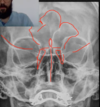

ANALISE A TOMOGRAFIA

Quando vaoms pensar em sinusite fúngica?

Quando temos, além da destruição do osso, presença de calcificações dentro da opacidade